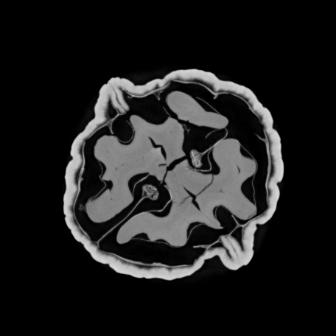

The numerical results are summarized in Table 1. These are evaluated in terms of peak signal-to-noise ratio (PSNR) and structural similarity index (SSIM) considering three different sampling settings, with different sparsity levels , angles, and noise set to 1% AWGN. It is evident that our method, TomoSelfDEQ, outperforms the competing approaches in terms of both PSNR and SSIM. In Fig. 1, we report the results obtained with the different methods considering 64 (top row), 32 (middle row) and 16 (bottom row) angles. We can see that with TomoSelfDEQ was able to reconstruct sharp and neat boundaries, even though some finer details are lost due to over-smoothing in certain regions. In addition, TomoSelfDEQ accurately reconstructs constant patches, without adding any significant artifacts and it proves to be stable with respect to the reduction of angles. On the other hand, FBP reconstructions are noisy and show an increasing number of streaking artifacts as the number of angles decreases. In the TV regularized reconstructions, the staircasing behavior is evident, and the sharpness of the boundaries deteriorates as the number of angles decreases. Sparse2Inverse produces reconstructions with clear artifacts, particularly when only 16 angles are considered.

Similar consideration can be drawn for the reconstructions in Fig. 2, where we show reconstructions of different walnut slices in the most challenging setting, i.e., with 16 angles. From the close-ups it is clear that Sparse2Inverse introduces numerous noisy artifacts, compromising the reconstructions, while TomoSelfDEQ better preserves objects shapes, significantly reducing noise presence. A note is, however, in order on the comparison with Sparse2Inverse. While both methods share key ideas such as operating in both image and projection domains, computing losses in the projection domain, and avoiding explicit nullspace assumptions, TomoSelfDEQ differs fundamentally in several important aspects. First, while Sparse2Inverse uses a standard U-Net architecture, our method leverages DEQ to implicitly represent an infinite-depth network. Second, TomoSelfDEQ provides theoretical guarantees about matching supervised performance, while Sparse2Inverse relies primarily on empirical validation. These theoretical and architectural advantages translate into practical improvements, as demonstrated in our numerical results where TomoSelfDEQ consistently outperforms Sparse2Inverse across different undersampling rates (cf. Table 1).